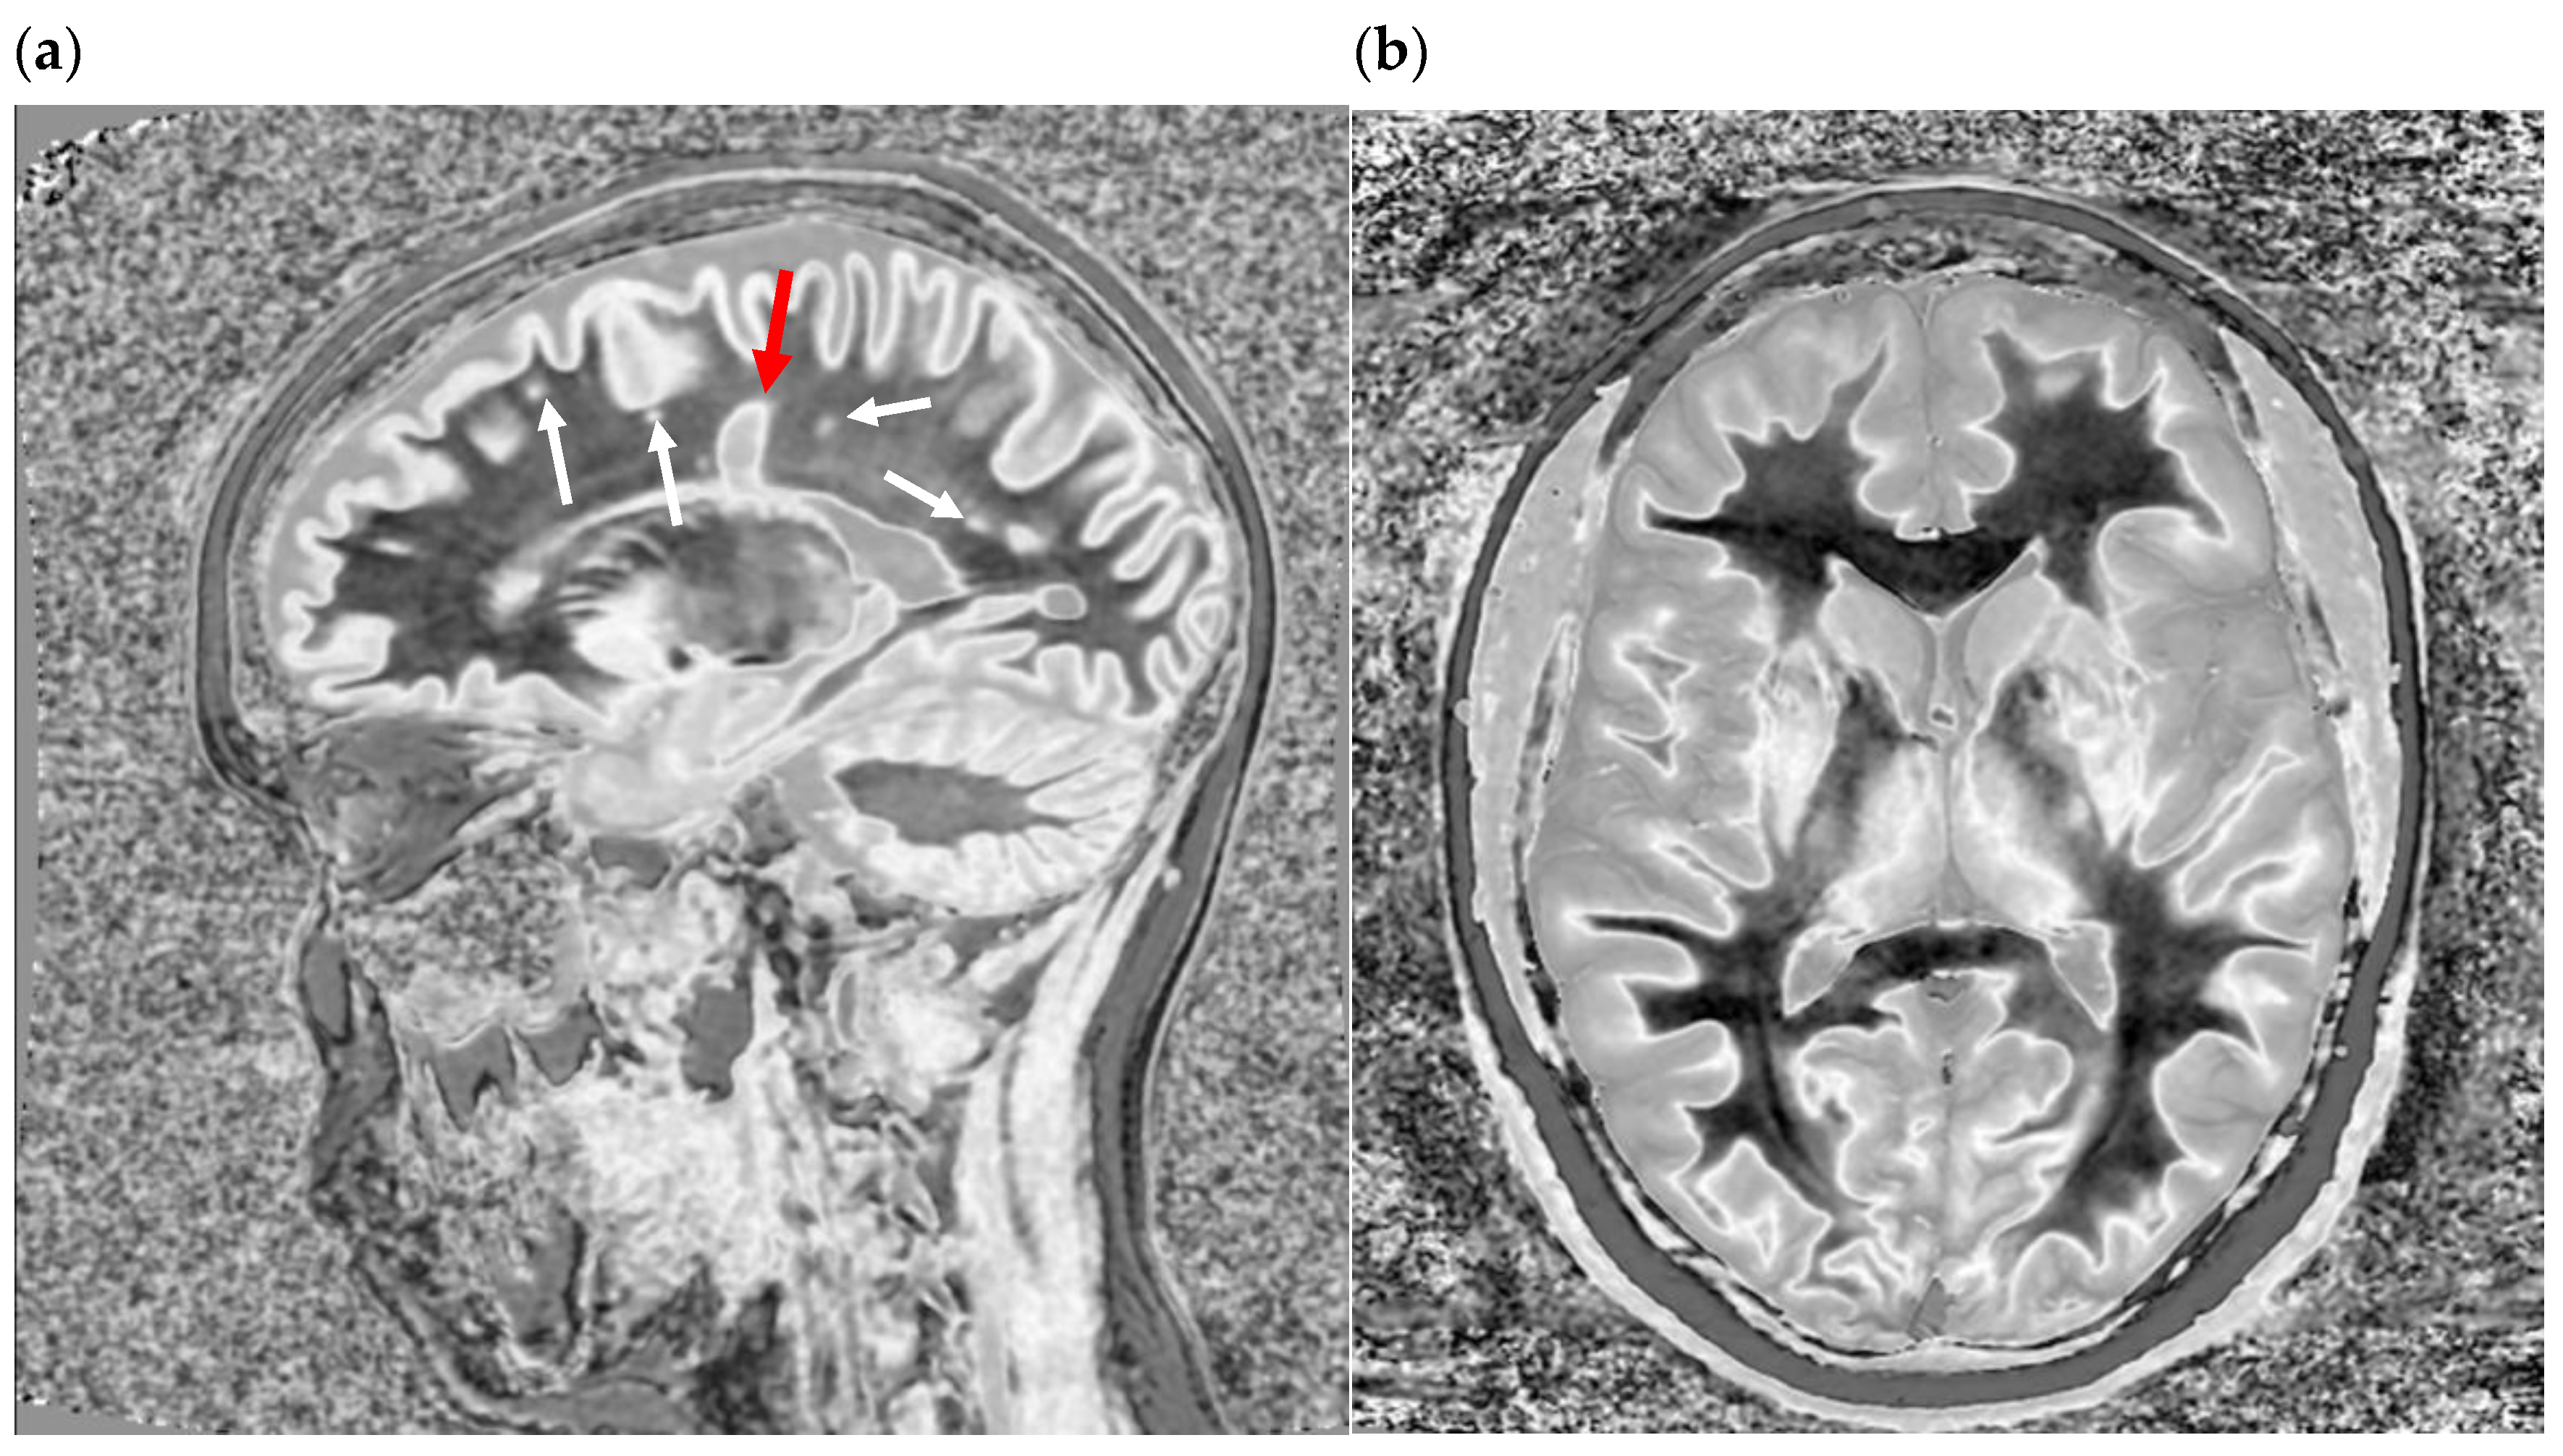

Figure 13.

Divided Subtracted Inversion Recovery (dSIR) in a patient with multiple sclerosis (MS). Three axial narrow middle domain images in a patient with an acute MS flare at the level of the centrum semiovale (left), corona radiata (middle), and basal ganglia (right). TIshort = 350 ms. TIlong = 500 ms. TE = 7 ms, TR = 5000 ms. The white matter is not black as in Figure 9b. There is a widespread increased signal, though not a “white out” sign as described in Figure 14. This is an “intermediate” appearance but not considered normal.